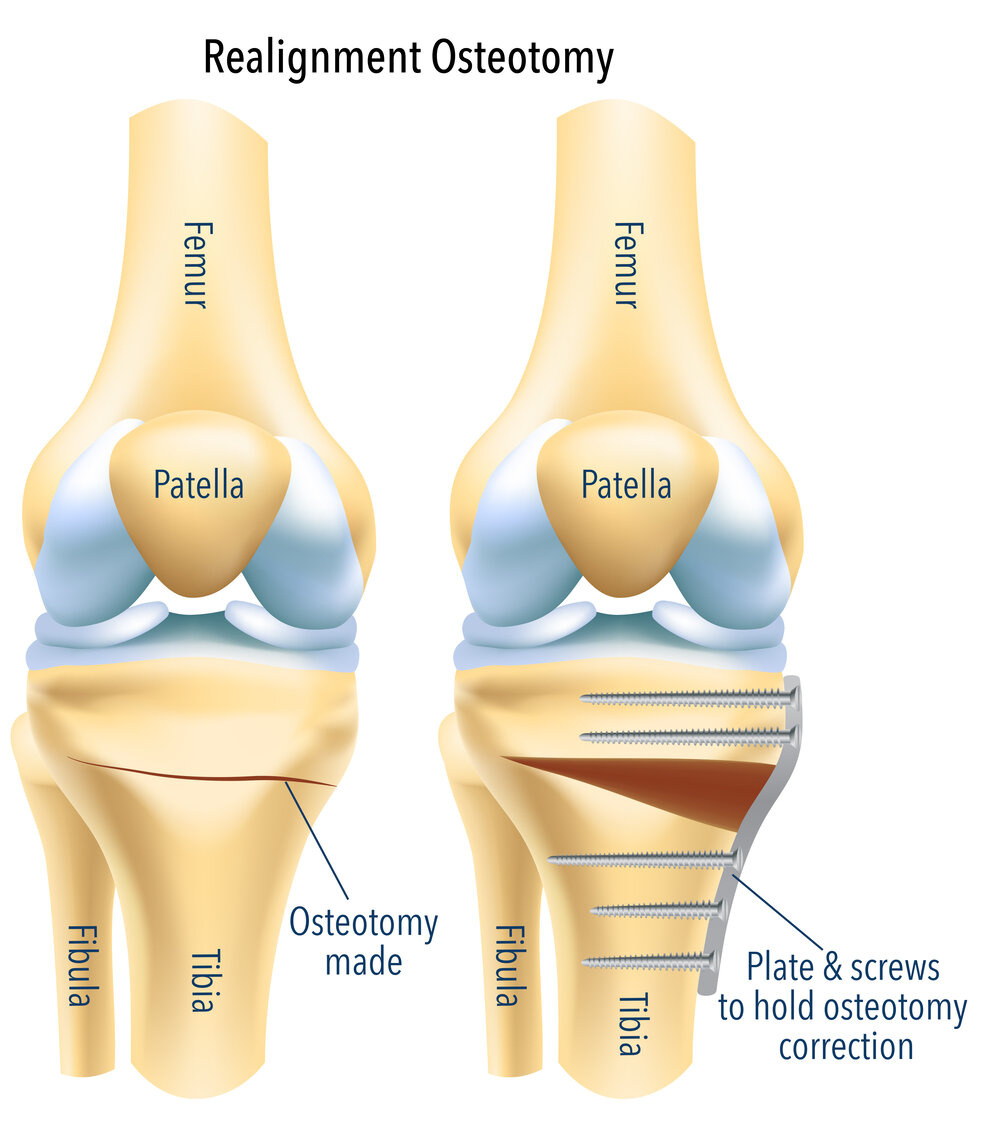

استئوتومی زانو

Osteotomy یک عمل جراحی است که به وسیله آن قسمتی از استخوان برش داده می شود، این کار برای تصحیح طول استخوان و یا راستای قرارگیری آن انجام می شود.

استئوتومی زانو برای آرتروز زانو اغلب برای افراد جوانتر ( کمتر از 50 سال) و فعال که آرتروز قسمت داخلی زانو و یا انحراف به داخل زانو و ساق پا(varus deformity) دارند انجام می شود. بیمار برای این روش درمانی نباید زیاد چاق باشد و خم و راست شدن زانو نباید محدودیت زیادی داشته باشد. البته شرایط دیگری هم هست که توسط جراحان محترم لحاظ می گردند.

بهبودی بعد از استئوتومی زانو معمولا طولانی ( حدود 10 سال ) هست، اگرچه تسکین علائم غالباً کامل نیست، اما استئوتومی ممکن است نیاز به تعویض کامل زانو را برای 5 تا 10 سال به تأخیر اندازد.